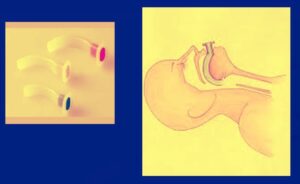

- Supraglottic airways: laryngeal mask airway LMA

- Supraglottic airway: i-gel

- Supraglottic airway: laryngeal tube